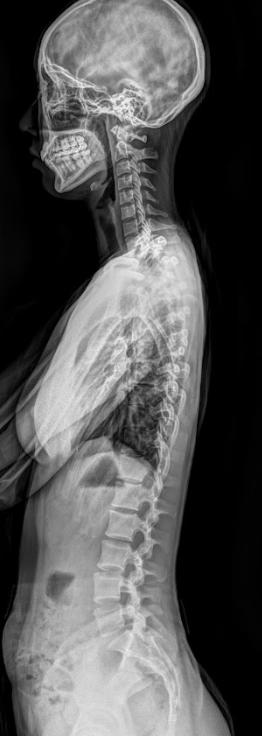

X-ray를 찍는 이유?

추체외로계 운동장애(디스토니아, 파킨슨증, 진전 등)는 주로 기저핵–뇌간 경로의 기능이상으로 발생합니다.

여기서 상부경추 변위로 뇌간에 압박이 생기면

망상체(reticular formation)

▶ 근긴장 조절 장애

전정핵(vestibular nuclei)

▶균형·자세 불안정

적핵(red nucleus)

▶ 미세운동 이상

▶ 불수의적 운동, 근긴장 이상

으로 이어질 가능성이 있습니다.

그래서 이러한 기능이상 파악을 위해 항상 X-ray로 상부경추(C0, C1, C2)의 정렬을 가장 먼저 확인합니다.

이는 정확하게 파악하고 치료하기 위함이며 상부경추(C0·C1·C2)의 회전 각도와 틀어진 방향을 수치화해

시술 전후의 변화를 비교하면 환자분이 느끼는 안정감이 실제 구조 변화와 함께 일치하는 걸 확인할 수 있기 때문이죠.